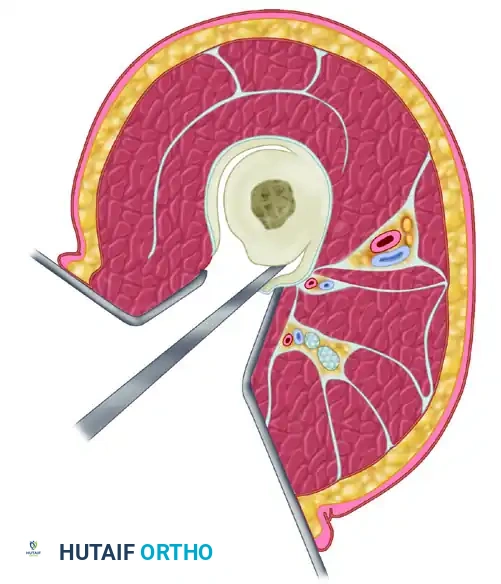

Judet and Patel Subperiosteal Decortication

For recalcitrant cases, Judet and Patel described an elegant biological technique: subperiosteal decortication. This involves elevating osteoperiosteal flaps (bone chips attached to the periosteum) around the nonunion site, followed by rigid internal fixation (plates or IM nails) with compression. In their series of 195 femoral nonunions, union failed in only 4.6% of cases.

Figure 59-24: Judet and Patel subperiosteal decortication. (A) Exposure of the femur, demonstrating autogenous bone chips elevated subperiosteally. (B) Cross-section illustrating the separation of cortical bone and periosteum from the femoral shaft.